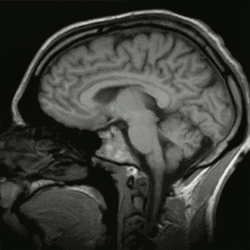

Brain Imaging

More recent research has sought to study the mindful brain (Hölzel et al., 2011; Taylor et al., 2011). Taylor et al. (2011) investigated the neural responses of individuals who practice mindfulness to emotional stimuli and compared results between experienced and beginner practitioners. Their results indicated that extensive mindfulness practice fosters emotional stability and modulates a number of regions in the brain that are involved in the neural responses to emotional experiences.

To confirm what mindfulness theory has long purported, the results of the study by Taylor et al. (2011) indicate that long term mindfulness practice induces brain activity patterns that are associated with acceptance of emotional stimuli and lower levels of interference from internal states (Taylor et al., 2011). The authors argue that this possibly points to better awareness of the here-and-now. Conversely, their results also indicate that less experienced mindfulness practitioners show brain activity that relates to voluntary regulation of emotion, which infers less acceptance of emotional states, and lower levels of emotional stability (Taylor et al., 2011).